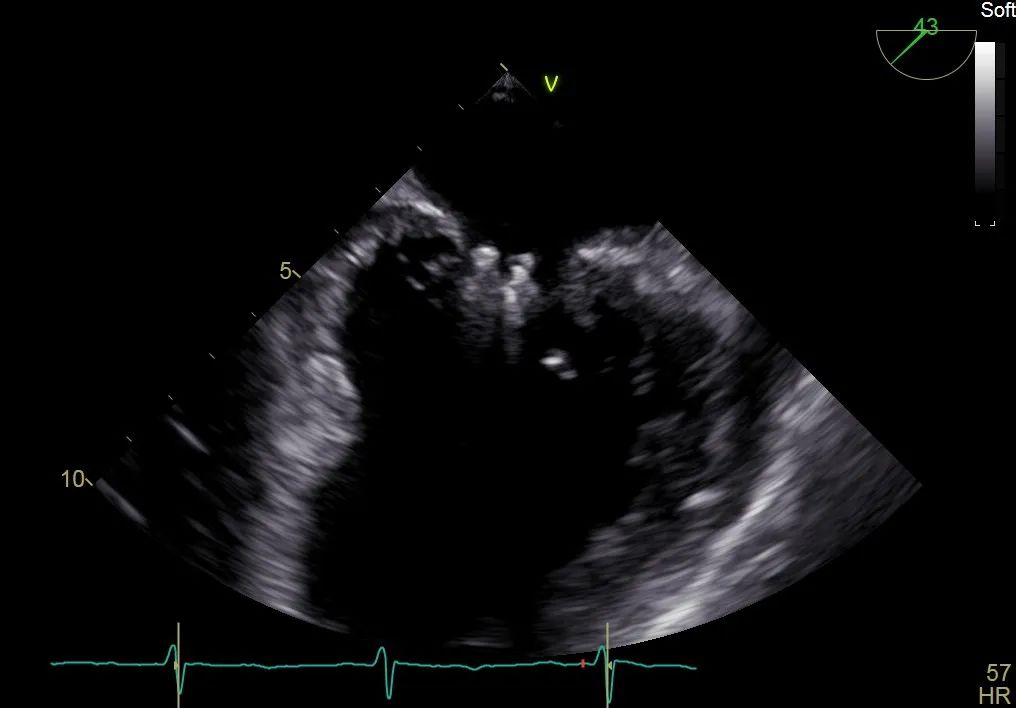

术前行经食道超声评估:继发性二尖瓣反流,反流程度4+;二尖瓣有效反流口面积(EROA) 0.81 cm²,缩流颈宽度18 mm,反流容积112.36ml,二尖瓣瓣口面积5.06 cm²,平均跨瓣压差5 mmHg,二尖瓣前叶(A2)长度15mm,二尖瓣后叶(P2)长度9 mm;左房内径54mm,左室收缩末期内径50mm,左室射血分数43%,肺动脉压83 mmHg。

术前食道超声可见二尖瓣重度反流,前后叶对合不全伴有间隙,且反流束宽度18mm